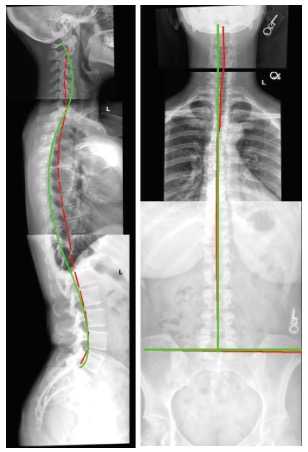

正常な背骨の形は、正面から見たら真っすぐで、側面から見たら頸椎(首)、胸椎(背中)、腰椎(腰)にそれぞれ適正なカーブがあります。それが長時間のパソコンやタブレット・スマホの使用や、悪い姿勢での座り方により、正面から見て真っすぐでなくなったり、側面から見て適正なカーブが失われてしまったりします。背骨の形が正常でなくなると、神経を圧迫して痛みやしびれ、動作障害を招きます。さらに免疫機能や自然治癒力が低下して精神面にまで悪影響を及ぼすそうです。

カイロプラクティックにはさまざまな治療法がありますが、CBP(Chiropractic BioPhysics)®は生物理学に基づいた高度な治療法です。ミッシマー先生のようにCBP®のライセンスを持ったドクターが、患者さんの姿勢とレントゲン写真を詳細分析し、背骨をより正常な形に戻す治療をします。背骨はより正常な形である方が体はうれしいので、患者さんは「CBP®治療は気持ちがいい」と言うそうです。骨のずれやゆがみは、日頃の姿勢の悪さが原因になります。ミッシマー先生はそれを防ぐための指導も行い、ヨガや筋トレも教えます。

座ってPC作業をすることが多い中、ある日突然左腰に小さな痛みを感じました。そこから数日であっという間に日常作業ができなくなるほどの激痛になってしまいました。ネット検索で「リサーチで実証された生物理学に基づくCBP治療法」を知り、すがる思いでミッシマー先生を受診。レントゲン分析で頸椎が逆カーブになっていること、背骨の一部がずれていること、腰椎のカーブがあり過ぎることが判明。レントゲン画像で明らかに自分の目で見て、どこが悪いのか即座にわかり、先生がどのような治療をすればいいのか明確に教えてくださったのでとても安心しました。そしてあんなに痛かった腰が、1回の治療で噓のようにまったく痛みがなくなり本当に驚きました。その後は、ずれや歪みを矯正する為に1ヶ月通院する中で、装置を使ったトラクション治療を行い、自宅では自分でできるデナロール矯正を毎日続け、先生に教えて頂いたヨガとストレッチを行いました。先生はあらゆることに知識が豊富で、丁寧かつ親身に治療してくださったので安心して通院することができました。先生には本当に感謝しております。これからも自宅でのトレーニングを続け健やかな心身を維持していきたいと思います。

レントゲン診断で痛みの原因を見極め、姿勢改善、背骨矯正によって根本治 療が可能。ストレートネックや側弯症に有効なCBP®治療を行っている。